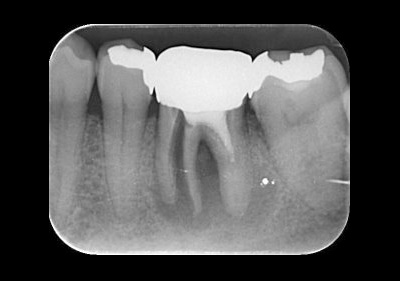

インプラント(骨造成術あり)

費用:50万円

治療期間:12ヶ月

メリット:隣の歯を削らない。歯と同じように噛める。

デメリット:骨、歯肉の状態では外科処置を数回行う場合あり。

治療前レントゲン![]() |